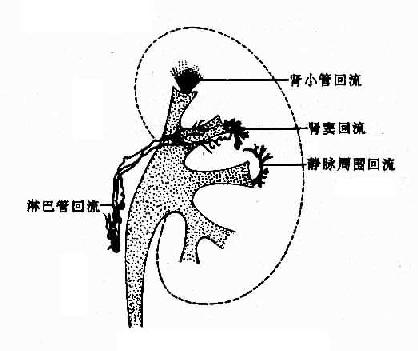

逆行肾盂造影,如注射压力过高会造成造影剂回流又称逆流或反流,入肾小管或血管周围等处,造成各种特殊的表现(图4-4-2)。应当避免造影剂回流。常见下数种回流:①肾小管回流,造影剂经乳头进入肾小管,表现为由肾小盏中心向皮质方向散布的放射状致密影;②肾窦回流,肾小盏穹窿部撕裂,造影剂回流入肾窦,表现为穹窿周围不规则角状或带状致密影,显著者出现一片不规则毛糙影;③血管周围回流,造影剂沿静脉周围间隙散布,表现为自穹窿向外走行的拱门状细条状影;④淋巴管回流,造影剂进入淋巴管,表现为纤细蜿蜒迂曲的线条影,向肾门方向行走。

图4-4-2 肾盂各种回流